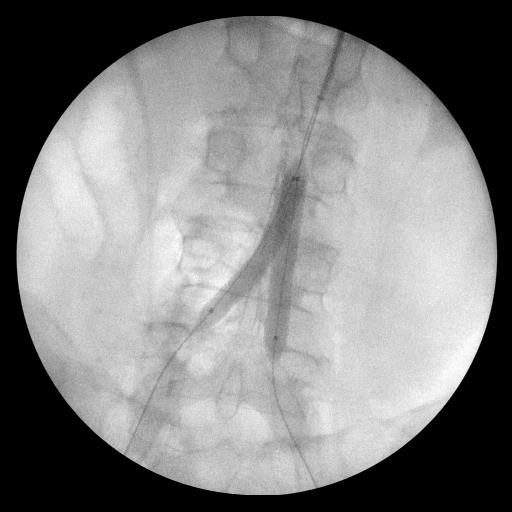

Субинтимальная реканализация